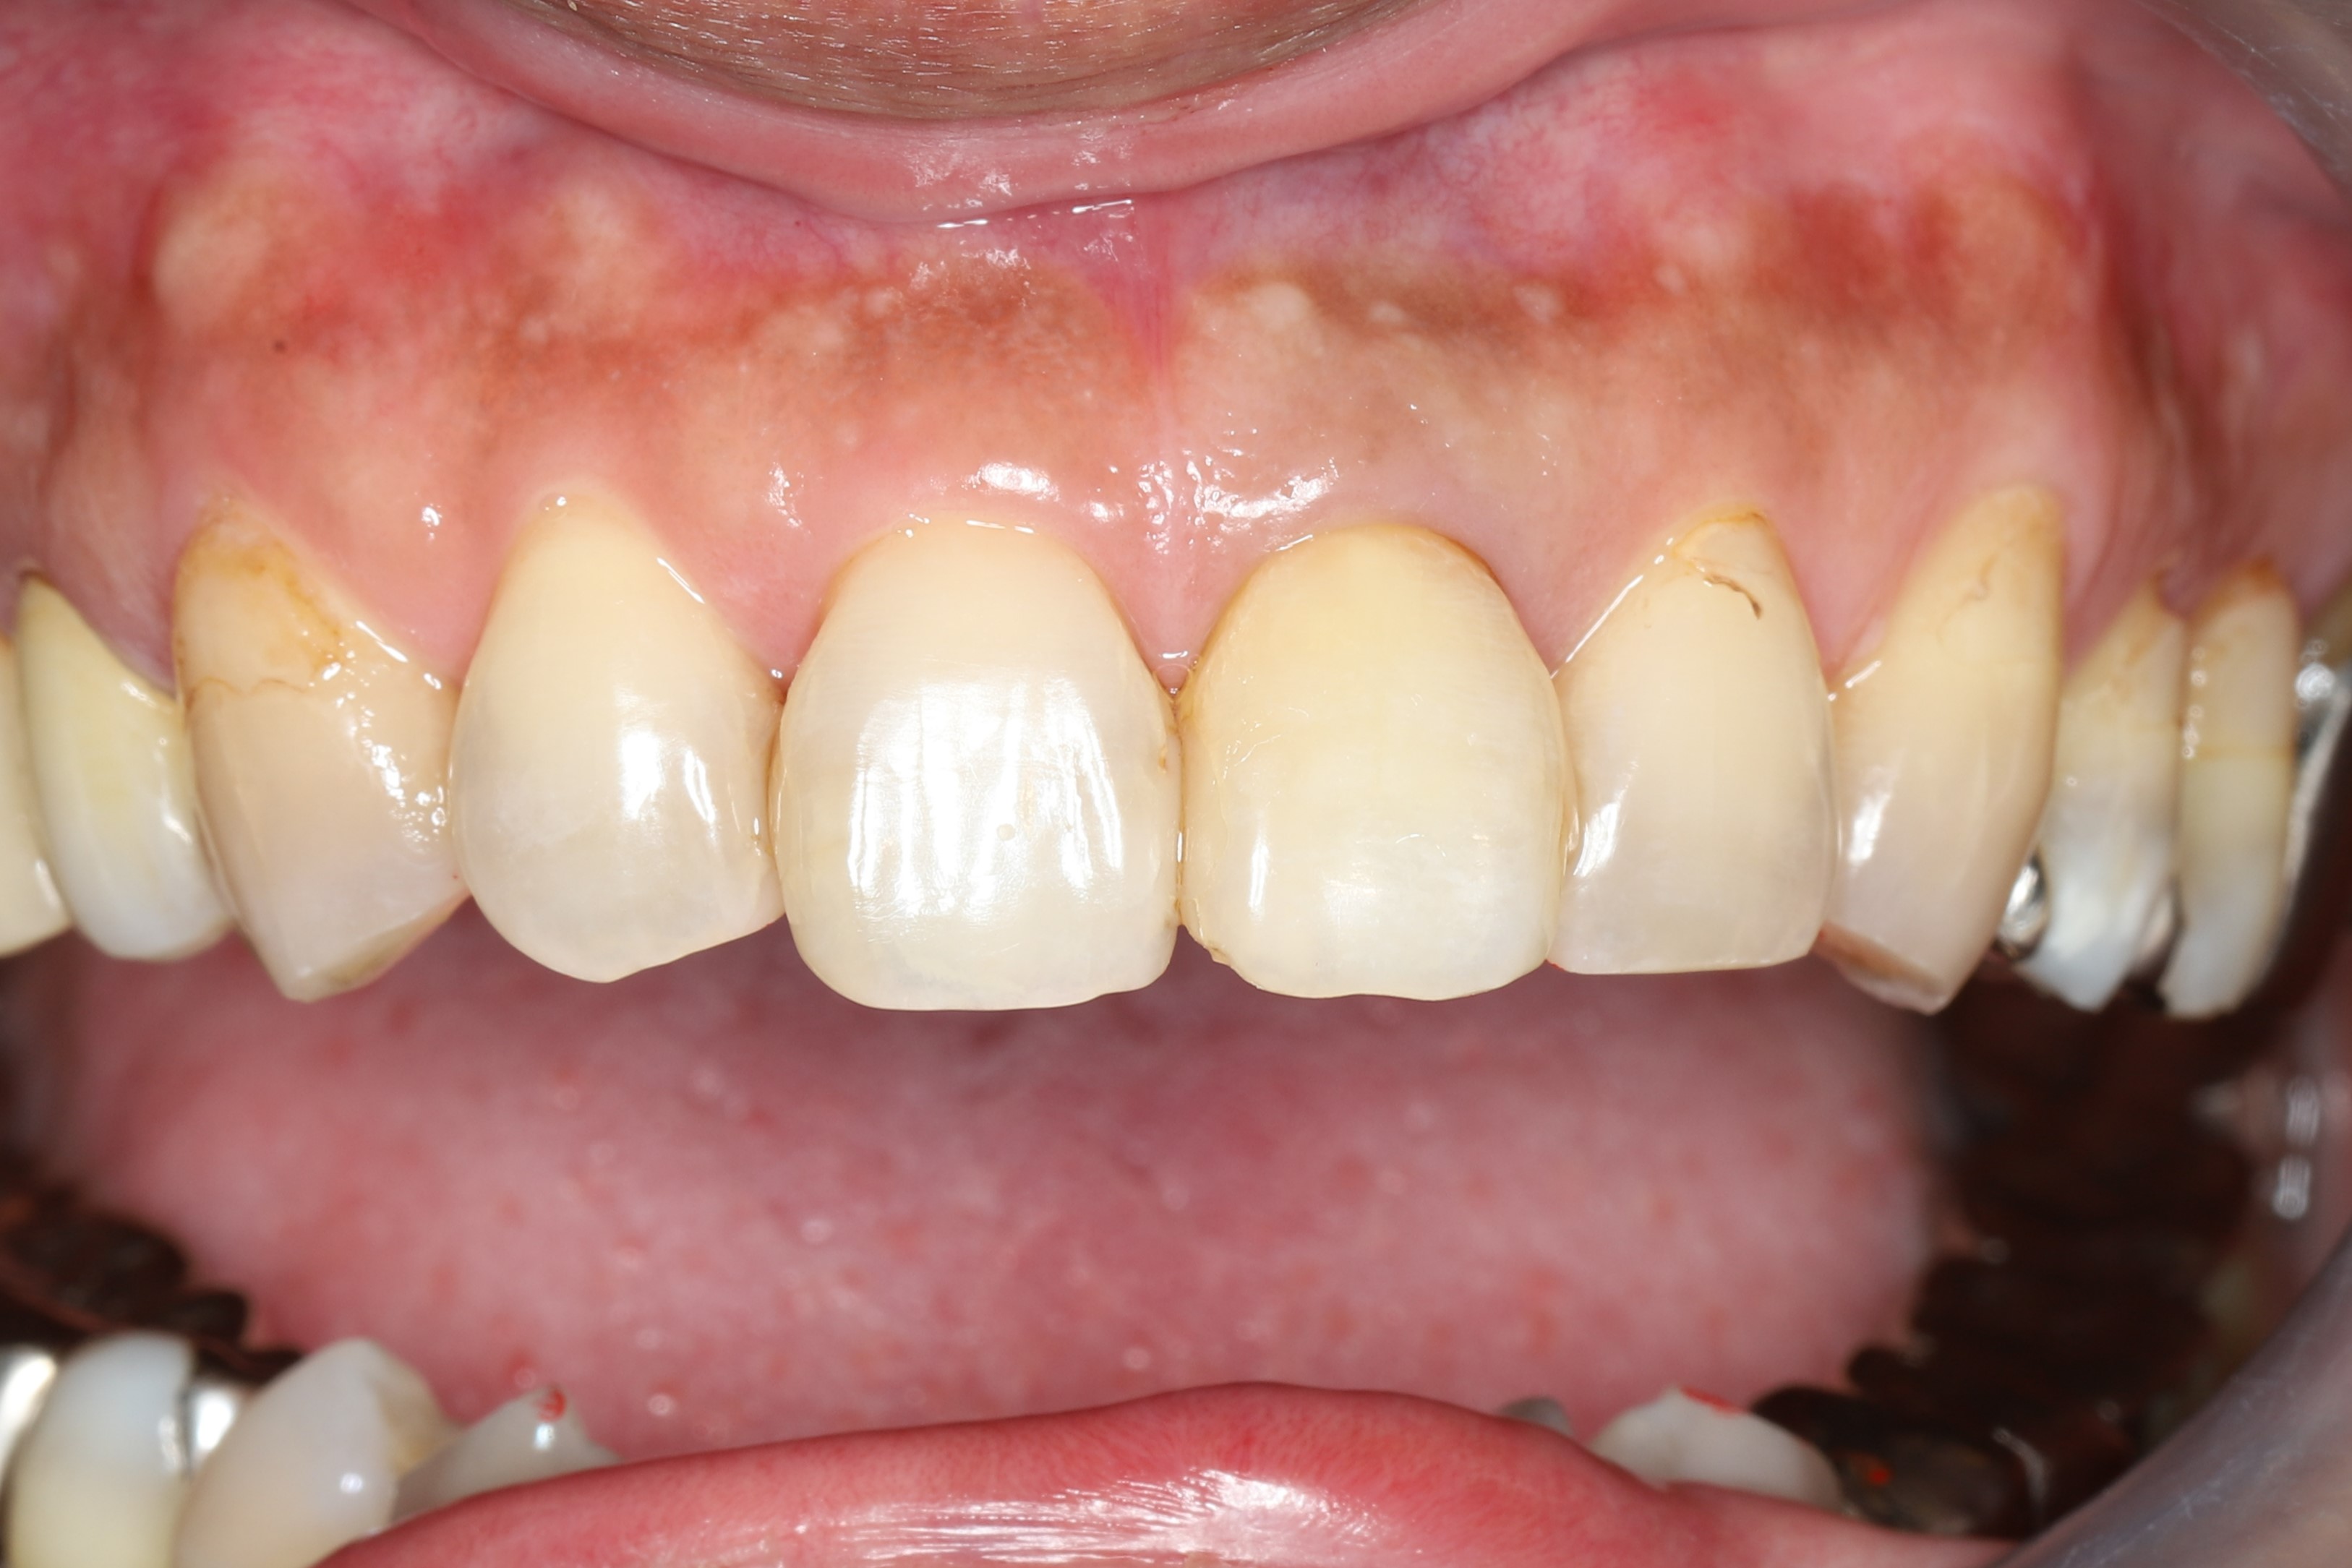

症例1(歯の色にのみ問題がある場合)

治療後(治療期間2ヶ月)